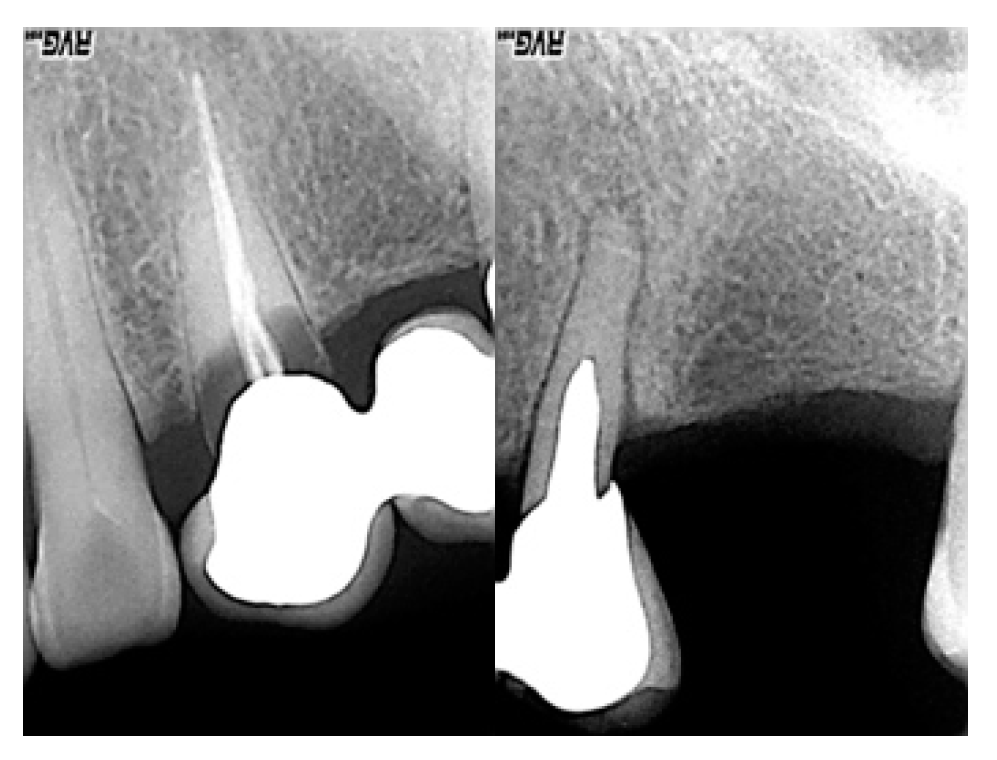

Intraoral X-ray examination: the lack of integrity and inconsistency of 2.3 and 2.5 (pillar elements of the fixed prosthesis) are highlighted (Figure 4).

Figure 4. Preliminary radiographs.

Prosthesis 02 00023 g004